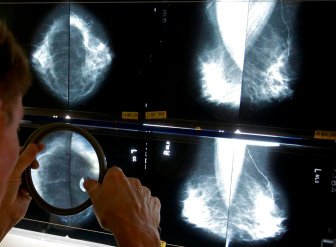

Mammograms

Alberta lowers age for women to be screened for breast cancerAlberta Health Services has lowered the recommended age for biennial breast cancer screening for average-risk women from 50 to 45.HealthOct 18, 2022

Cancer foundations in Saskatchewan launch fundraiser to save the ‘Breast Screening Bus’Since 2002, the Breast Screening Bus provided mammograms for residents in rural and remote communities of Saskatchewan, but funding is now needed for a new bus.HealthOct 3, 2022

15 patients in N.L. require followup as review of thousands of mammograms continuesThe province's health authorities have identified 15 patients this week requiring further followup as a review continues of thousands of mammograms.HealthSep 15, 2022

‘How the hell did this happen?’ More than 16,500 mammograms under review across N.L.Officials from three of the province's four health authorities told reporters the approximately 13,884 mammograms under scrutiny represent about 11,751 patients.HealthAug 31, 2022

Newfoundland health authority reviewing about 3,000 mammograms for possible issuesThe health authority will review its mammogram viewing procedures and look at whether this error occurred because staff had been working from home during the COVID-19 pandemic.HealthAug 24, 2022

Disabled women in Quebec still struggling with mammogram access: advocatesA community group advocating for people with disabilities claims some women are having trouble getting access to mammograms.CanadaMay 4, 2022

AI can spot breast cancer better than humans, study findsArtificial intelligence programs are better at spotting cancer than humans, a new study suggests. What does that mean for cancer detection?HealthJan 1, 2020

Many women aren’t told they have dense breasts. Here’s why it matters43 per cent of women ages 40 to 74 have dense breasts, and they can have serious implications.LifestyleOct 3, 2019

New breast cancer screening guidelines are outdated and dangerous, experts sayMore than 130 breast-cancer doctors and researchers disagree with new screening recommendations, saying the task force is basing their recommendations on outdated data.HealthJan 28, 2019

Patients should decide when to get mammograms: Canadian health expertsNew guidelines from the Canadian task force on preventive health are empowering women to take charge of their health when it comes to breast cancer screening.HealthDec 10, 2018